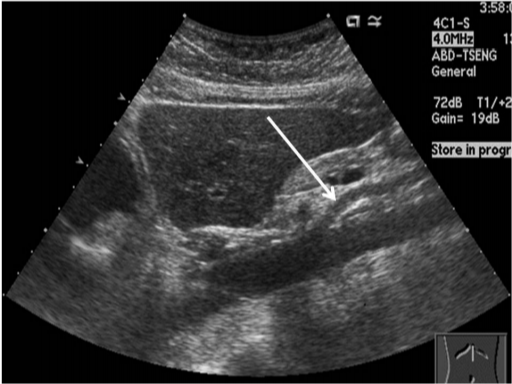

신장(콩팥) 질환

- 신장 결석

- 수신증